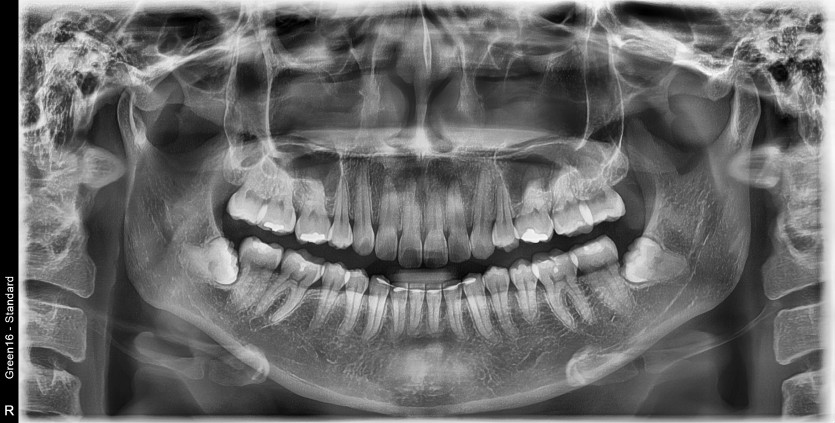

#48 사랑니 발치

구강 외과 전문의가 당일 발치했습니다.